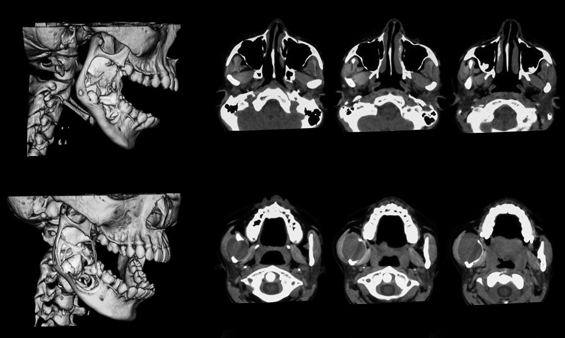

TC / TAC Articulação Temporo-Maxilar

É um exame indolor que utiliza Raio-X para obter informação sobre diferentes pontos do corpo, e que depois do processamento computorizado dos dados obtidos, permite uma imagem em diferentes planos da zona da face.

Este exame é realizado em 2 fases, uma de boca fechada e outra de boca aberta.